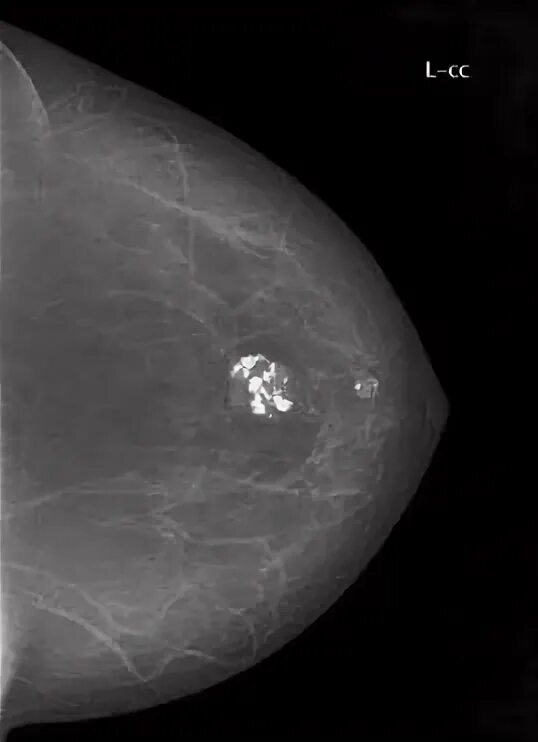

Как выглядит киста молочных желез